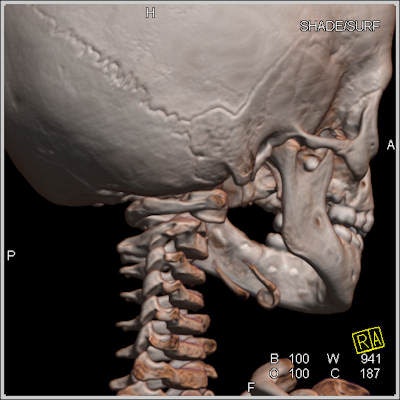

"Give me your bones and I'll tell you who you are," said Dedouit, who showed how CT can be used to identify corpses destroyed beyond recognition in crashes, or skeletons found in the woods, thanks to anatomical signatures, such as prostheses that match radiological records and even jewelry fused to the body. Half of all identification matches are made with radiographic records of the thorax, and a quarter is based on variations in anatomy.